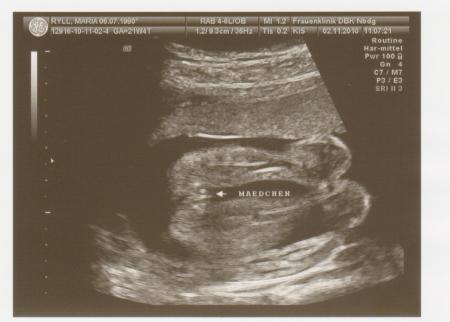

Hallo ihr Lieben, ich bin ganz begeistert Feinsono war echt toll! Es bleibt 100% beim Mädchen-Outing und es gab keine Auffälligkeiten!!! Sie sagte das es ein zierliches Mädchen ist, aber alle Werte sind im Normbereich. Aber mein Mann und ich sind ja auch weder groß noch kräftig gebaut. Sie ist jetzt 24,8cm groß und 367gr schwer. Der werdende Papa ist auch hin und weg. Hab ganz viele Bilder bekommen. Ein paar hänge ich euch mal an. liebe Grüße